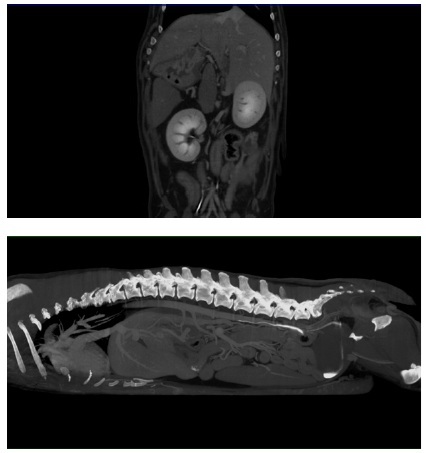

Les scanners classiques fonctionnent avec un mouvement hélicoïdal en mesurant usuellement 1 mm et en extrapolant 1 mm informatiquement. Ce tomodensitomètre atteint le plus haut niveau d’évolution de la technologie CT à écran plat, offrant une imagerie diagnostique de qualité pour les tissus durs et mous. Grâce à sa technologie HDVI, cet appareil d’examen tomodensitométrique exclut l’interpolation en réalisant 100 % de mesure pour créer une reconstruction en 3 dimensions (3D) complète

Il est particulièrement adapté aux Nouveaux Animaux de Compagnie (NAC) en raison de sa rapidité de mesure (une mesure en 22 secondes) et de sa précision au dixième de millimètre près. Un technologie de faisceaux coniques (Cone Beam Technology) permet de réduire l’exposition de l’animal.